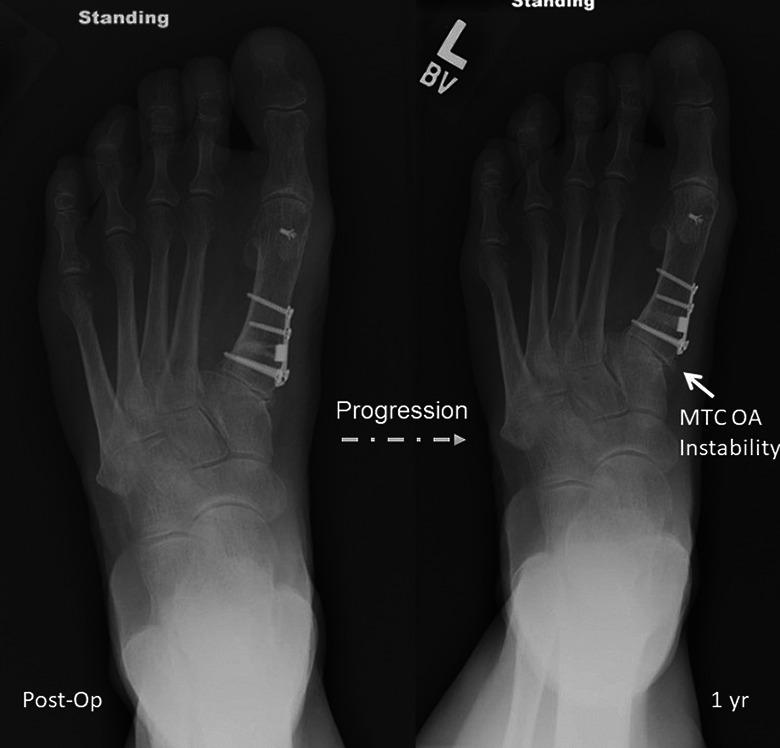

Fourteen feet (13 patients; 2 male and 11 female, average age 56 years, range 22-75) with hallux valgus underwent an opening-wedge osteotomy of the medial cuneiform fixed with a low-profile nonlocking wedge plate combined with distal soft tissue realignment. The mean preoperative hallux valgus angle (HVA) was 32 degrees and the IMA was 16 degrees. HVA, 1-2 IMA, proximal first metatarsal inclination (PFMI), and presence of osteoarthritis of the first TMT joint were assessed on preoperative and final postoperative radiographs. Final postoperative radiographs were also evaluated for radiographic union and hardware failure at an average of 7 months (range, 3-19 months) postoperatively.

A mean intraoperative correction of 19 degrees and 7 degrees was achieved for the HVA and IMA, respectively. The mean HVA was 22 degrees and the mean IMA was 11 degrees at the time of final follow-up. At final follow-up, a recurrence of the deformity was observed in 12/14 feet. There were 2 nonunions-one plate failure and one screw failure. No first TMT joint instability or arthritis was observed. All patients were ambulatory without assistive device in either fashionable or comfortable shoe wear.

Medial cuneiform opening-wedge osteotomy resulted in unreliable correction of HVA and IMA at short-term follow-up with a high rate of early recurrence of hallux valgus deformity and a complication rate similar to that of the Lapidus procedure. This procedure cannot be recommended for addressing hallux valgus in the setting of increased obliquity of the first TMT joint.